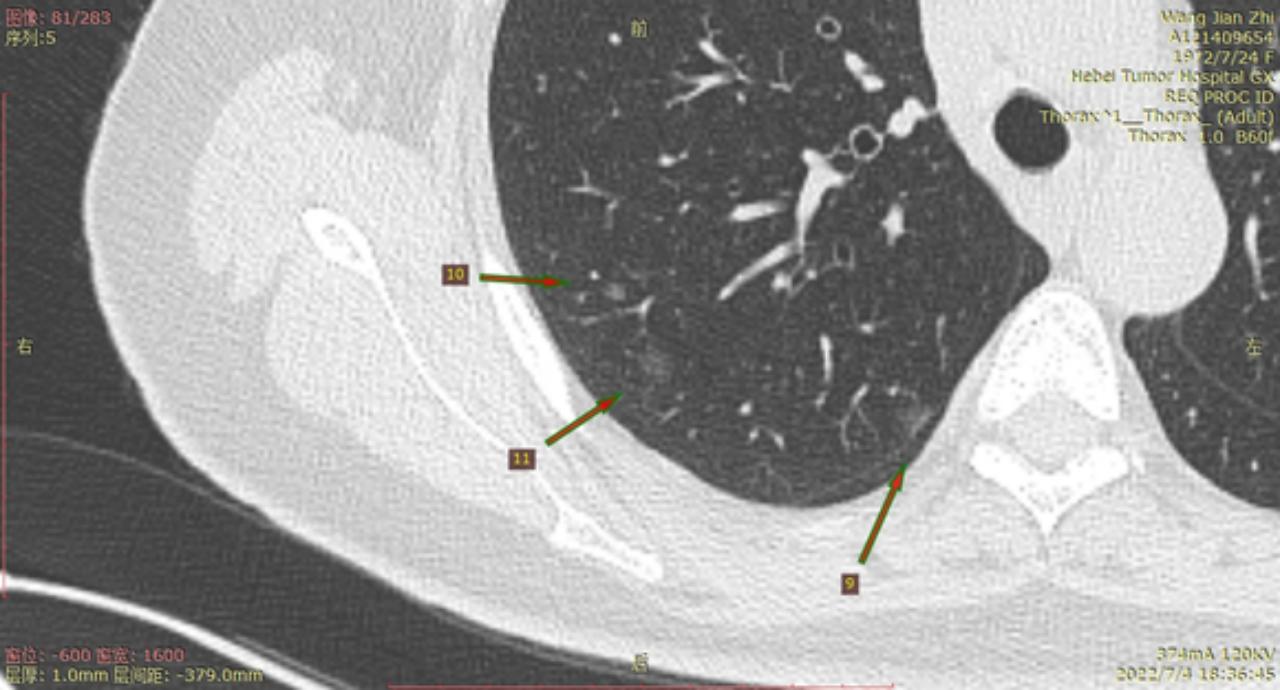

今年6月22号河北省人民医院进行CT检查后,报告双肺多发磨玻璃结节及微小结节以右肺为多,建议六个月后复诊。我于7月3号在河北省四院胸外科就诊,大夫建议复查薄层CT,7月4日CT结果报告示两肺多发结节,部分为磨玻璃密度,建议三个月复查,省四院的主任看了CT后有的建议立即住院手术,有的建议三个月复查,专家意见不一致,后来我看了主任的贴吧,首次发现肺结节先口服莫西沙星,三个月后再复查的贴吧,就没有立刻手术,从7月4日开始口服莫西沙星,现已完成15天疗程。等待复查的这一段时间里,总是担心大的结节已有浸润,请主任给予帮助,看看我的CT,给出我治疗建议,麻烦主任了!

结4-5

结8-11